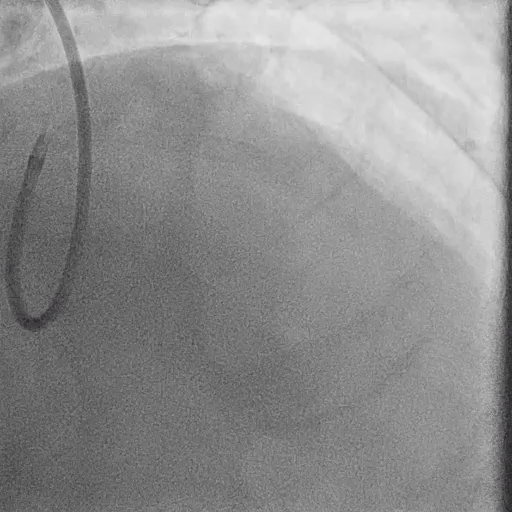

Post LM-LAD PCI

IVUS: good stent apposition, no edge dissection, minimal overlying strut at Ostial LCx

MSA: LM 11.23 mm², POC 10.86 mm², Ostial LAD 9.94 mm²

Post-PCI LAD FFR: 0.93

Final Angiography

Excellent vessel expansion and blood flow